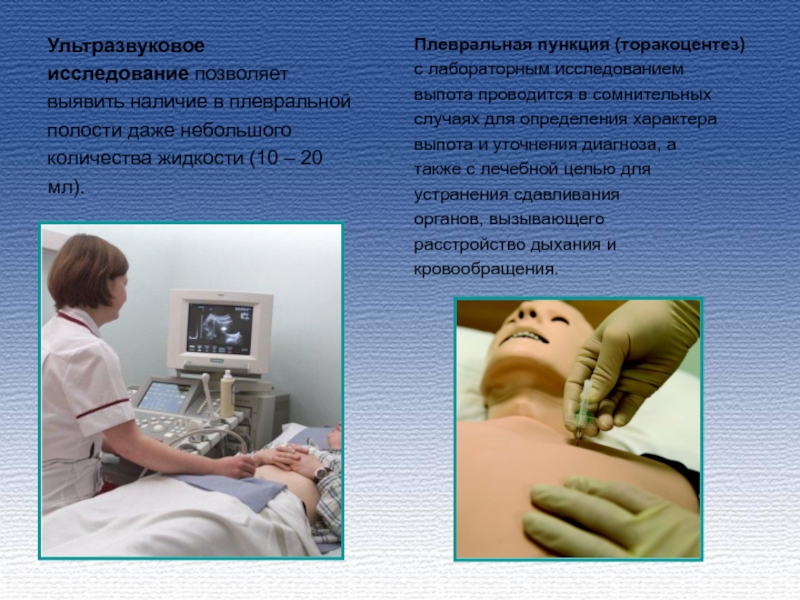

Диагностика плеврального выпота: что нужно знать